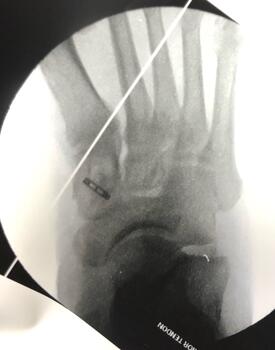

Next, the surgeon identifies the dorsal aspect of the medial cuneiform and centralizes a guide wire on the bone using intraoperative fluoroscopy. The guide wire placement is perpendicular to the dorsal cortex and advanced bicortically. One directly visualizes and confirms via fluoroscopy the position and orientation of the guide pin, exercising caution to prevent penetrating the proximal or distal joints.

Drilling of an appropriately sized bone tunnel then takes place over the guide wire in the medial cuneiform from dorsal to plantar, being careful not to penetrate the plantar cortex. One then threads the suture limbs (from the previously placed whip stitch) through the cortical button, and the button inserter advances the button through the medial cuneiform from dorsal to plantar. Fluoroscopy confirms the button has flipped and is in proper position, sitting flush against the plantar cortex (see fifth and sixth photos above). The tendon is then carefully brought into the tunnel and advanced by pulling the sutures with controlled tension. Once the tendon is in satisfactory position, with the appropriate tension, insertion of a tenodesis screw further secures the tendon in place.